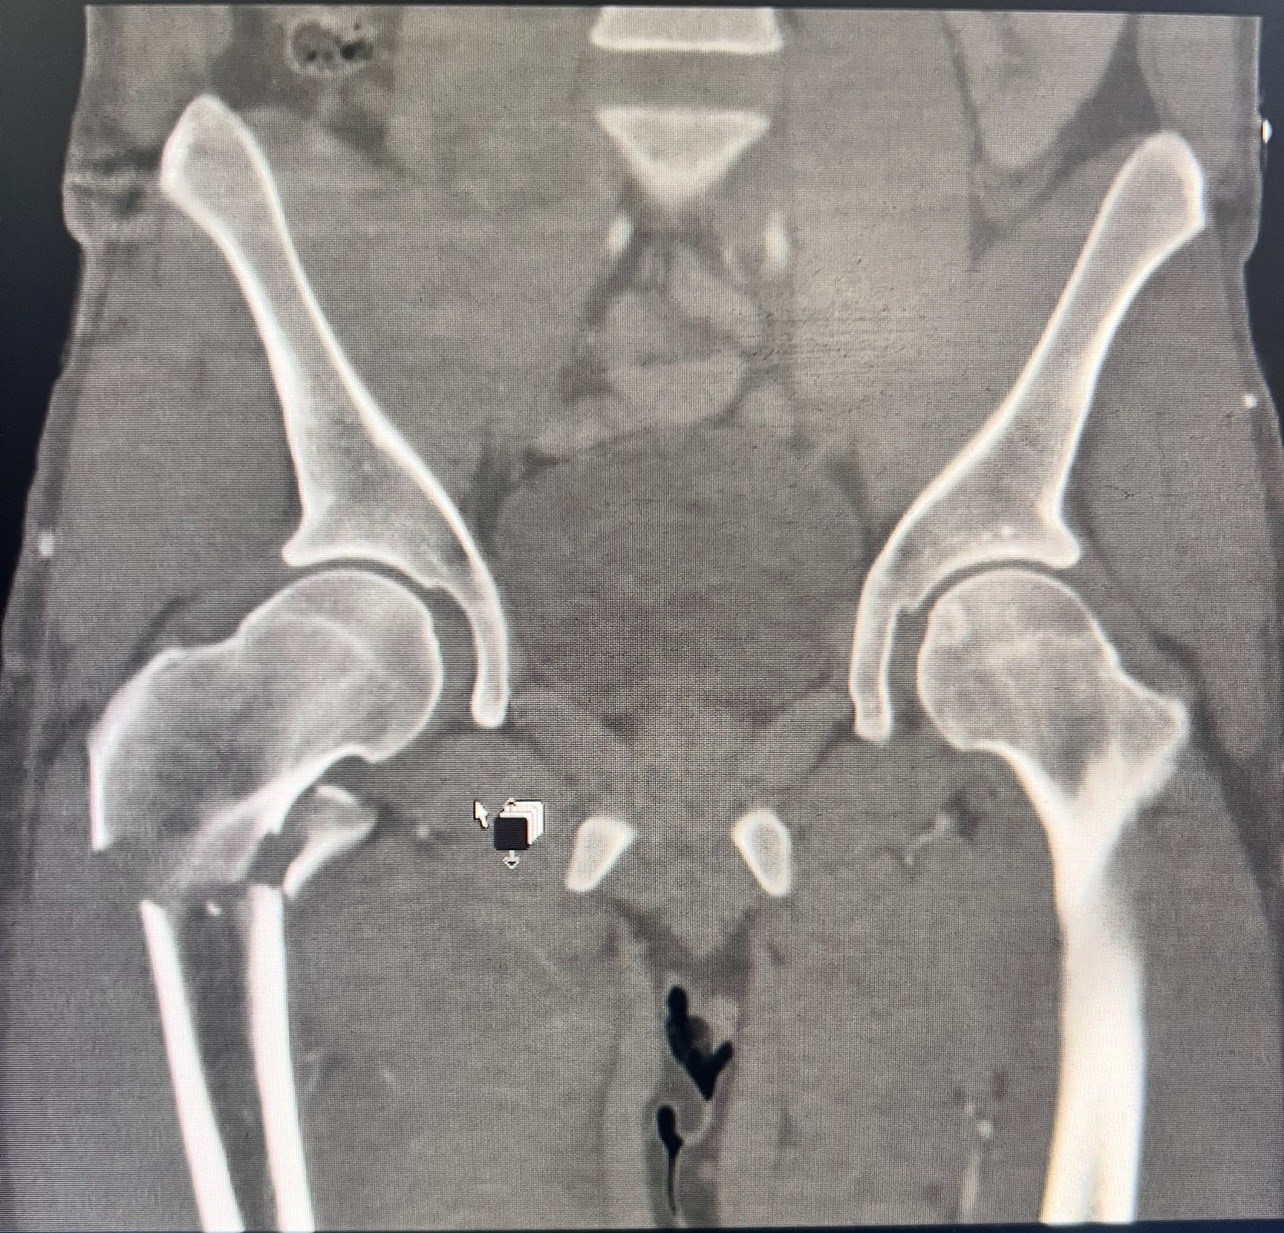

Earlier this month, I had a serious kitesurfing accident that left me with a broken femur. After surgery, I’ve been told I’ll be off my feet and out of work for at least 6–8 weeks.